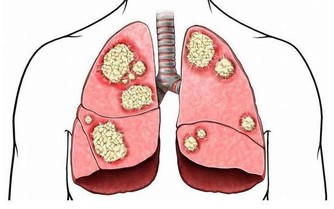

2、肥胖和營養不良

甜食吃太多,會造成寶寶肥胖,甚至引發糖尿病等代謝疾病。

甜食還可消耗體內的維生素,使唾液、消化腺的分泌減少,胃酸增多,引起消化不良。

孩子吃多了甜食還會挑食偏食,造成營養不良。